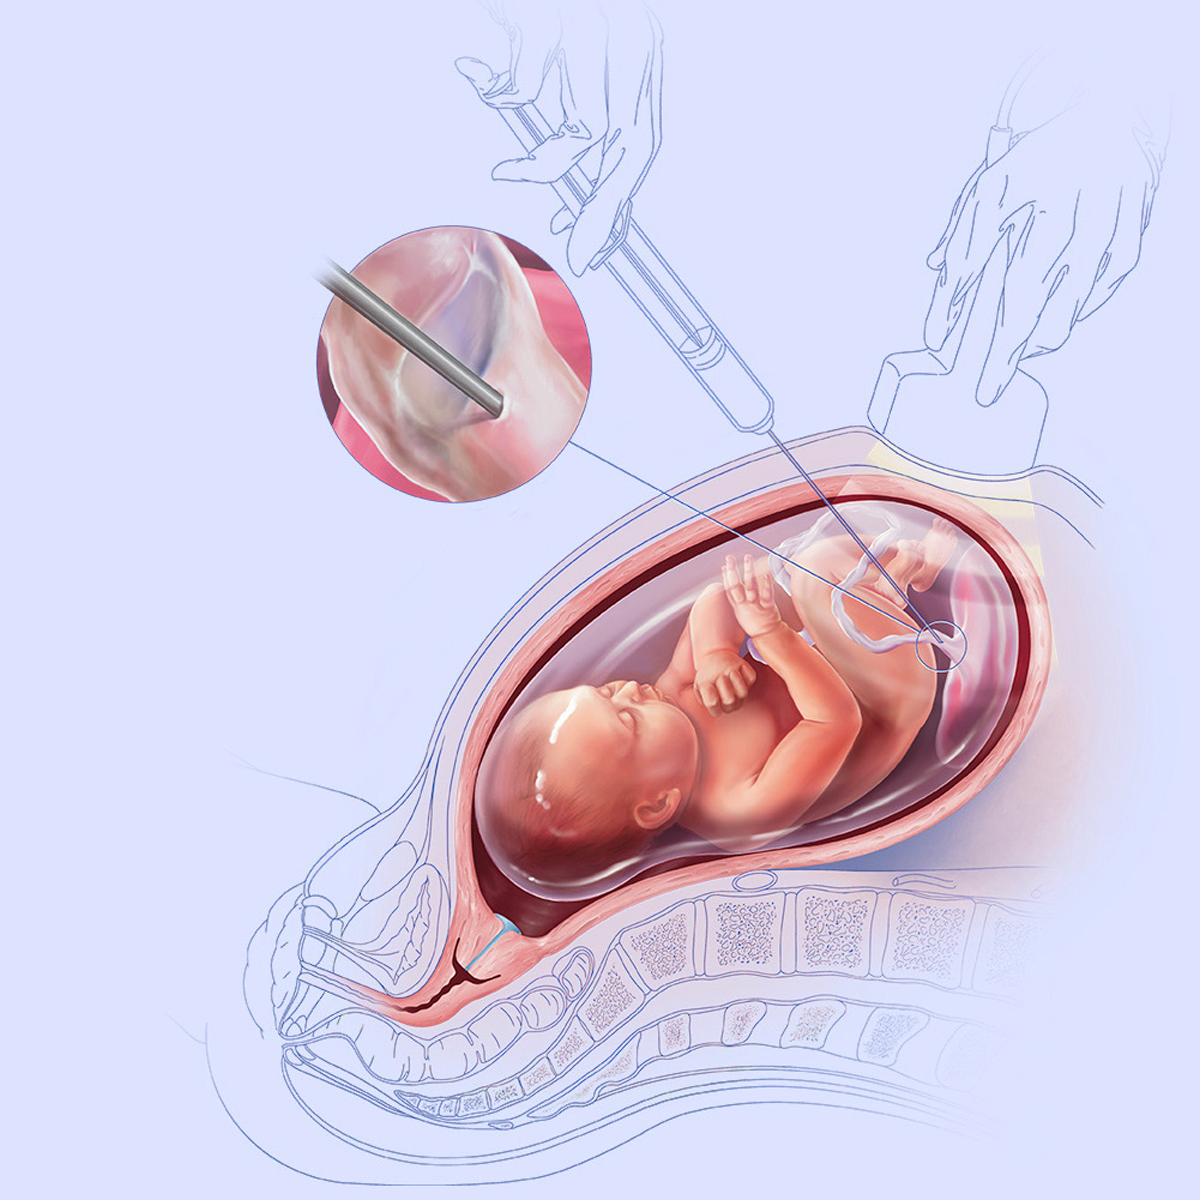

1. Amniocentesis

Amniocentesis is the procedure where fluid around the baby in the womb (amniotic fluid) is aspirated by inserting a very thin needle in mother’s abdomen (like taking a blood sample from the arm). The procedure is associated with a small risk of miscarriage (0.1%) above the background risk.

CVS is the procedure where sample form placenta is obtained by inserting a very thin needle in mother’s abdomen. The procedure is associated with a small risk of miscarriage (0.1%) above the background risk.

Cordocentesis is done to obtain fetal blood in cases of fetal anaemia, risk of haemoglobinopathy / metabolic disorders, at times for fetal karyotype if amniotic fluid is scanty.

In cases of fetal anaemia, like, Rh isoimmunisation; cross-matched blood is given to the fetus in – utero.